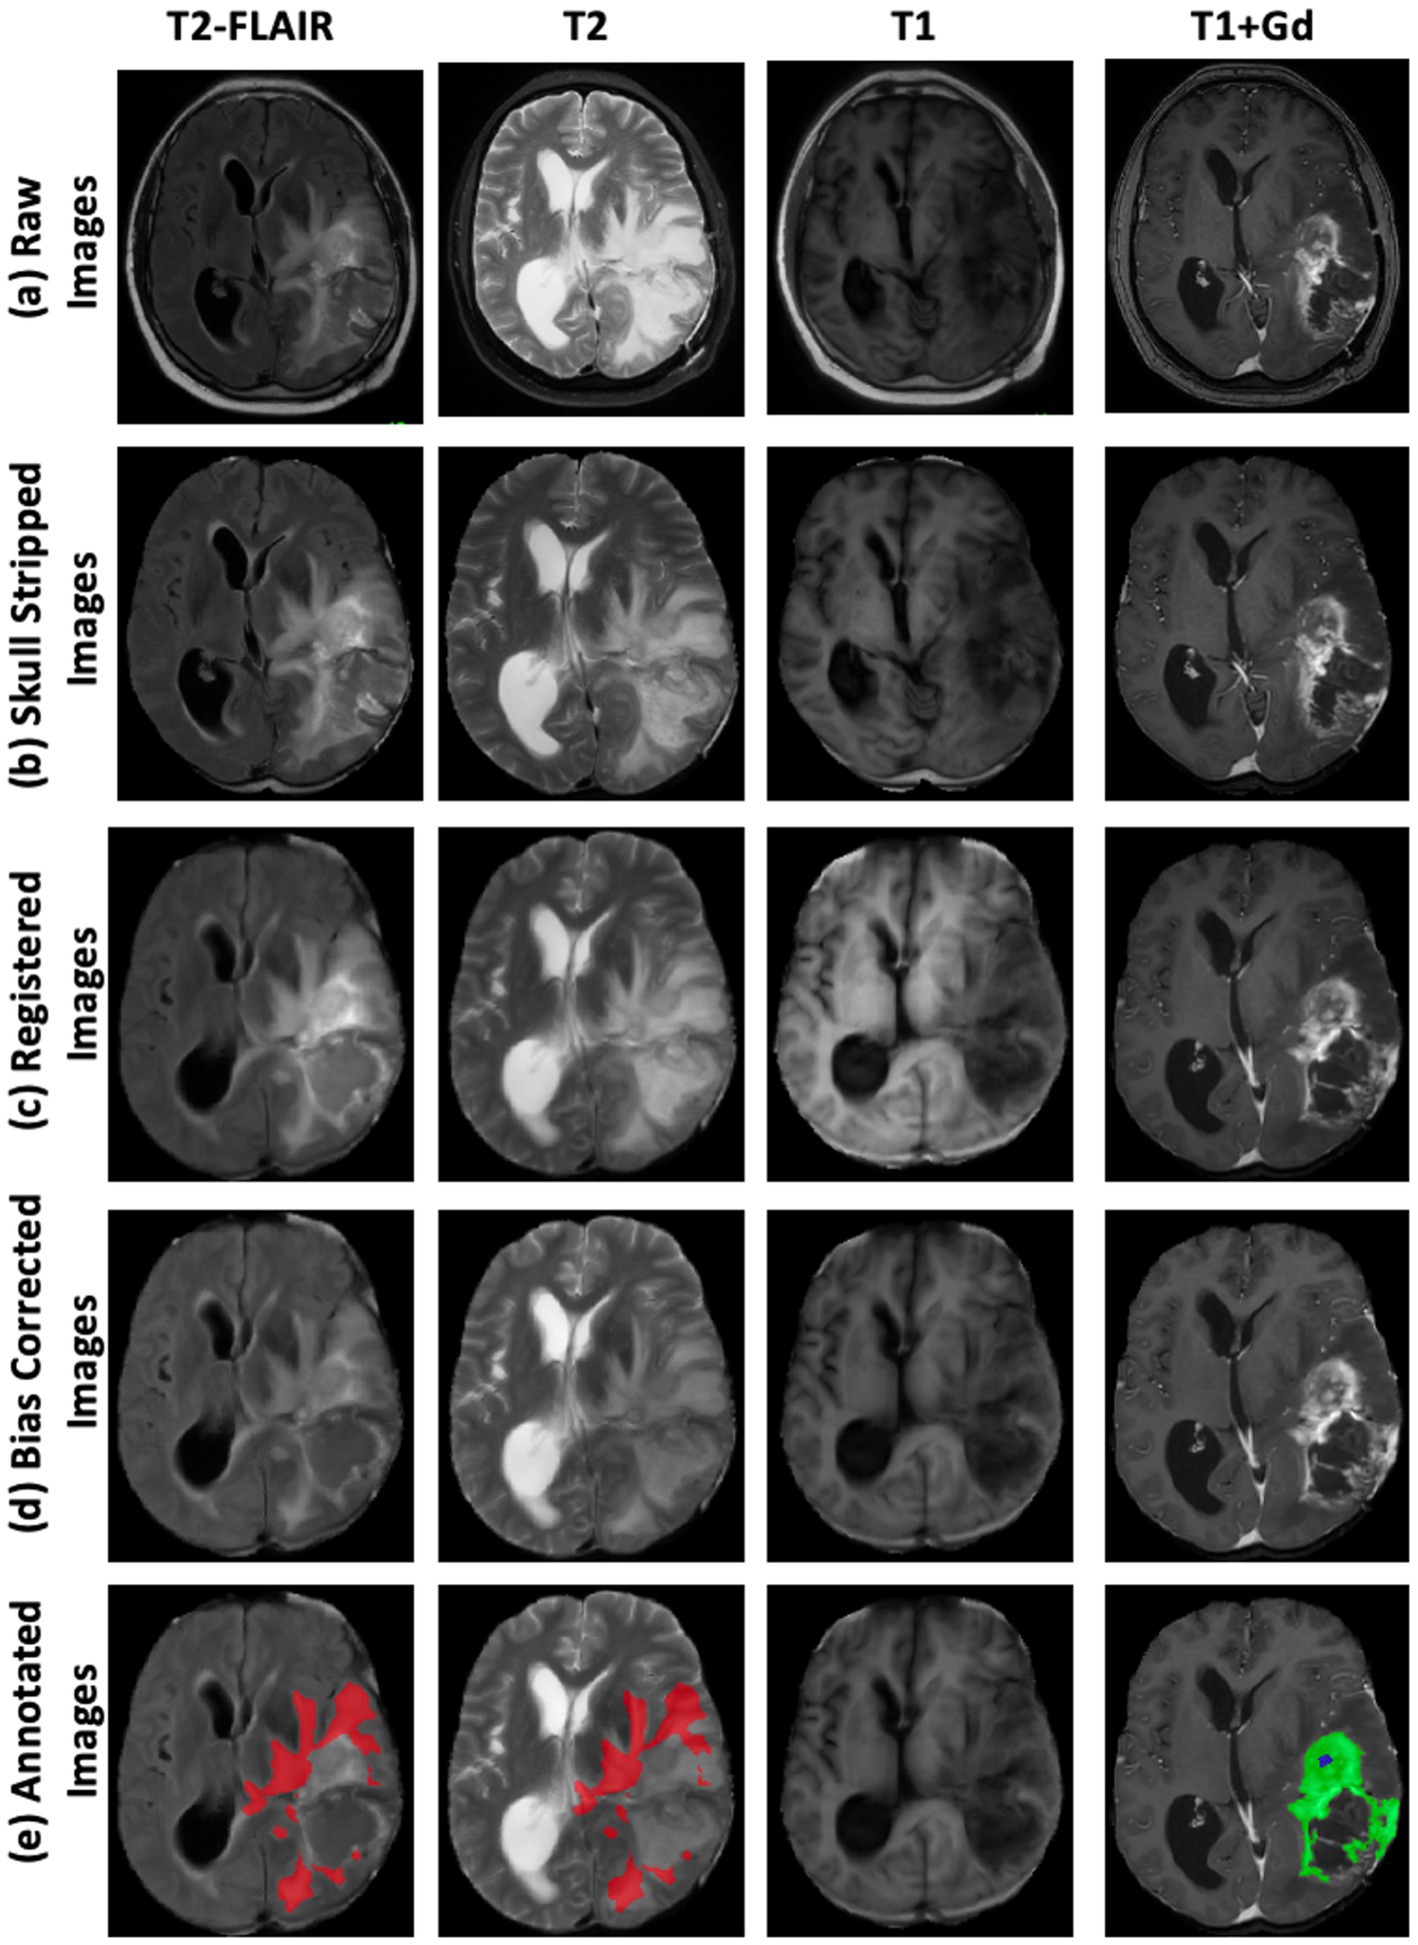

The following steps—skull stripping, image registration, and bias correction—were performed to minimize the effects of varying magnetic fields and image resolution, as illustrated in Figures 1a–d.

• Skull stripping: The Simple Skull Stripping (S3) (Roy and Maji, 2015) method was used to remove the skull from all four MRI modalities. The S3 method uses the SRI24 template (Rohlfing et al., 2010) to estimate the brain area and create a mask to extract brain tissue.

• Image registration: FreeSurfer (Fischl, 2012) was employed to register the MRI scans using the SRI24 template, ensuring the data were geometrically aligned (Toga and Thompson, 2001). This step facilitates consistent anatomical alignment across the different imaging modalities. We employed FreeSurfer’s MRICoreg with a 12-degree-of-freedom affine transform to align each MRI scan to the SRI24 template. This configuration accounts for translations, rotations, scaling, and shear, thereby ensuring geometric consistency across subjects and scanners. Registration was performed with the following parameter settings: spatial scales of 2 and 4 voxels, a maximum of 4 iterations, function tolerance of 1.0e-07, line minimization tolerance of 1.0e-03, and a saturation threshold of 9.999e+01. The estimated transforms (.lta files) were subsequently applied using FreeSurfer’s ApplyVolTransform, which by default performs resampling with trilinear interpolation into the template space.

• Bias correction: N4 Bias Field Correction (Tustison et al., 2010) (SimpleITK) was applied to mitigate low-frequency intensity inhomogeneities introduced by scanner hardware and acquisition protocols. The N4 algorithm iteratively estimates a smooth multiplicative bias field and normalizes image intensities, thereby improving uniformity and enhancing the reliability of intensity-based feature learning. We used the default parameter settings of the N4BiasFieldCorrection function in SimpleITK: input pixel type = sitkFloat64, maximum number of iterations = 50 (per level), bias field full width at half maximum = 0.15, number of histogram bins = 200, mask label = 1, shrink factor = 4, and convergence threshold = 0.0.

Figure 1. Step-by-step preprocessing pipeline for multi-modal brain MRI data. Columns display four MRI sequences: T2-FLAIR, T2-weighted, T1-weighted, and T1-weighted with gadolinium contrast enhancement (T1 + Gd). Rows illustrate sequential preprocessing steps: (a) Raw Images—original MRI scans acquired directly from the scanner; (b) Skull-Stripped Images—removal of non-brain tissues to isolate intracranial structures; (c) Registered Images—alignment of all modalities to a common spatial reference frame for voxel-wise correspondence; (d) Bias-Corrected Images—correction of intensity inhomogeneities to improve image uniformity and facilitate analysis; (e) Annotated Images—expert tumor labels overlaid on bias-corrected images, where Fluid Attenuation Inversion Recovery (FLAIR) Hyperintensity Regions (red), Enhancing Tumor Regions (green), and Non-Enhancing Central Necrosis Regions (blue).

After image preprocessing, the MRIs were transferred to the neuro-radiology workstation for semi-automatic volumetric analysis and tumor segmentation. This analysis was conducted by a neuro-radiology researcher and a clinical fellow, with each case meticulously supervised by a board-certified neuroradiologist. ITK-SNAP (2019, version 3.8) was used to generate segmentation ground truth. Segmentation was carried out using an automatic region of interest (ROI) tool, which selects pixels within a specified signal intensity range. Once the automatic ROI was generated, the neuro-radiologists manually refined the ROIs, excluding areas incorrectly included in the volumetric analysis. Segmentation was performed across four MR sequences simultaneously. T1 and T1 + gadolinium (Gd) were used to segment the NENR and ER. T2 and T2-FLAIR were used to identify FHR. Each scan labeled three tumoral regions: FHR, ER, and NENR. Figure 1e illustrates a sample image with labeled regions.